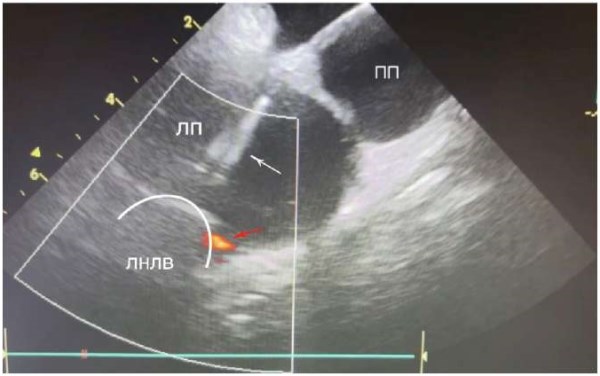

Рис. 8. Криобаллон раздут в левой нижней ЛВ. Красной стрелкой указан «leak» по нижнему краю баллона. Белая стрелка — шифт в полости ЛП.

Сокращения: ЛНЛВ — левая нижняя легочная вена, ЛП — левое предсердие, ПП — правое предсердие.